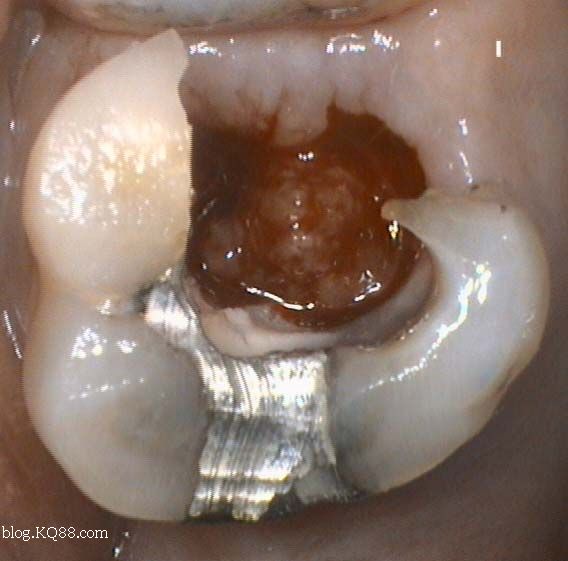

如何判斷牙齒牙洞已經(jīng)深入到牙髓?,牙齒牙洞深度判斷,如何確定已影響牙髓?

1、口腔鏡檢查:通過口腔鏡檢查,可以清晰地觀察到牙齒表面的牙洞以及牙洞內的情況,醫(yī)生可以判斷牙洞是否已深入牙髓,并評估病情嚴重程度。

2、探診檢查:使用牙科探針檢查牙洞周圍組織的健康狀況,了解牙洞深度及與牙髓的關系。